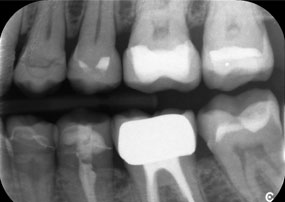

Dr. Wolfgang Tautschnig, ein erfahrener Zahnarzt aus Salzburg, hat die Synea Power Edition über mehrere Monate hinweg in seiner Praxis in verschiedenen klinischen Szenarien eingesetzt und evaluiert. Darunter vor allem für das Entfernen von Zirkonkronen und das Bearbeiten von unedlen Legierungen. In einem konkreten Fall stellte sich eine 81-jährige Patientin mit dem Wunsch nach einer ästhetischen Verbesserung ihrer 40 Jahre alten VMK-Kronen vor. Die bestehenden Kronen entsprachen nicht mehr den ästhetischen Ansprüchen der Patientin. Die Herausforderung lag in der Entfernung von zwölf verblockten Kronen mit unedler Legierung, ohne die darunterliegenden Zahnstümpfe zu beschädigen. Das Winkelstück wurde genutzt, um die Keramikschichten präzise einzuschlitzen sowie die Metallgerüste mit einem Hartmetallfräser zu trennen, um so die Kronen mit minimalem Trauma zu entfernen. Innerhalb von nur 30 Minuten waren die alten Kronen entfernt, danach konnte die neue Arbeit, bestehend aus Vollzirkon im Seitenzahnbereich und verblendeten Kronen im Frontzahnbereich, vorbereitet werden. Das Ergebnis war eine vollständige Neuanfertigung, die sowohl funktional als auch ästhetisch überzeugte (siehe Abb. 1).

Ein weiteres Beispiel für die klinische Leistungsfähigkeit der Power Edition war der Austausch einer beschädigten Zirkonkrone bei einer 63-jährigen Patientin. Diese stellte sich aufgrund eines abgesplitterten Verblendungsteils ihrer 20 Jahre alten Zirkonkrone an Zahn 6 vor. Trotz der Position im Seitenzahnbereich empfand die Patientin dies als störend und wünschte eine neue Krone.

Die Power Edition ermöglichte eine präzise Schnittführung, wobei das erhöhte Drehmoment und die verbesserte Kühlung dazu beigetragen haben, die Krone ohne größeren Materialverlust zu entfernen. Das Spannsystem und das verbesserte Drehmoment erwiesen sich hierbei als essenziell.